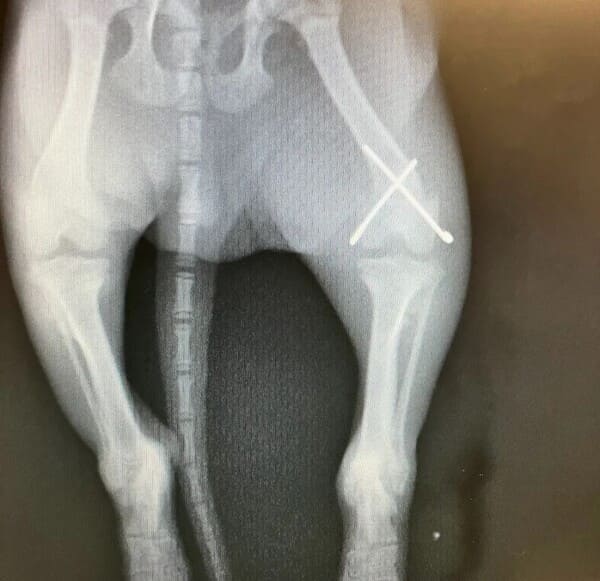

El veterinario ortopedista utiliza una variedad de herramientas avanzadas, como radiografías, resonancia magnética (MRI), tomografía computarizada (CT), ecografías y artroscopias, para diagnosticar y tratar problemas ortopédicos en mascotas. Estas tecnologías permiten obtener imágenes detalladas de huesos, articulaciones y tejidos blandos, facilitando un diagnóstico temprano y preciso. Con esta información, diseña planes de tratamiento personalizados que mejoran la eficacia y reducen el tiempo de recuperación, asegurando que tu mascota reciba la mejor atención posible para recuperar su salud y bienestar.

radiografía